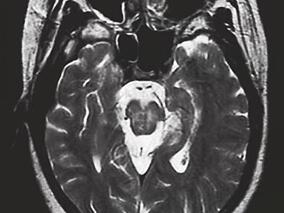

1小时条评论【病例资料】 患者,女性,20岁。因智能减退、左侧肢体僵硬20个月、左上肢震颤及抽搐发作10个月,加重伴右侧肢体僵硬和震颤4个月于2004年8月25日收入院。 现病史:患者自2003年初学习成绩开始下降,之后逐渐出现左侧肢体僵硬、活动不灵。2003年11月出现左上肢震颤...